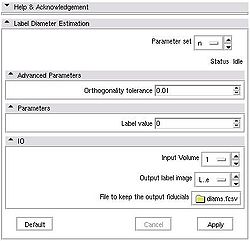

Quick Tour of Features and Use

The module also outputs numeric values for the lengths of the computed diameters. To see these numbers, open Log Viewer, and select the first from top log record with the name Label Diameter Estimation: standard output. The reported numbers are the lenghts of the three diameters, the volume estimate calculated as A*B*C/2 (a formula suggested in the literature for estimating volume of hematomas from planimetric measurements [2]), and the true label volume in mm^3. |